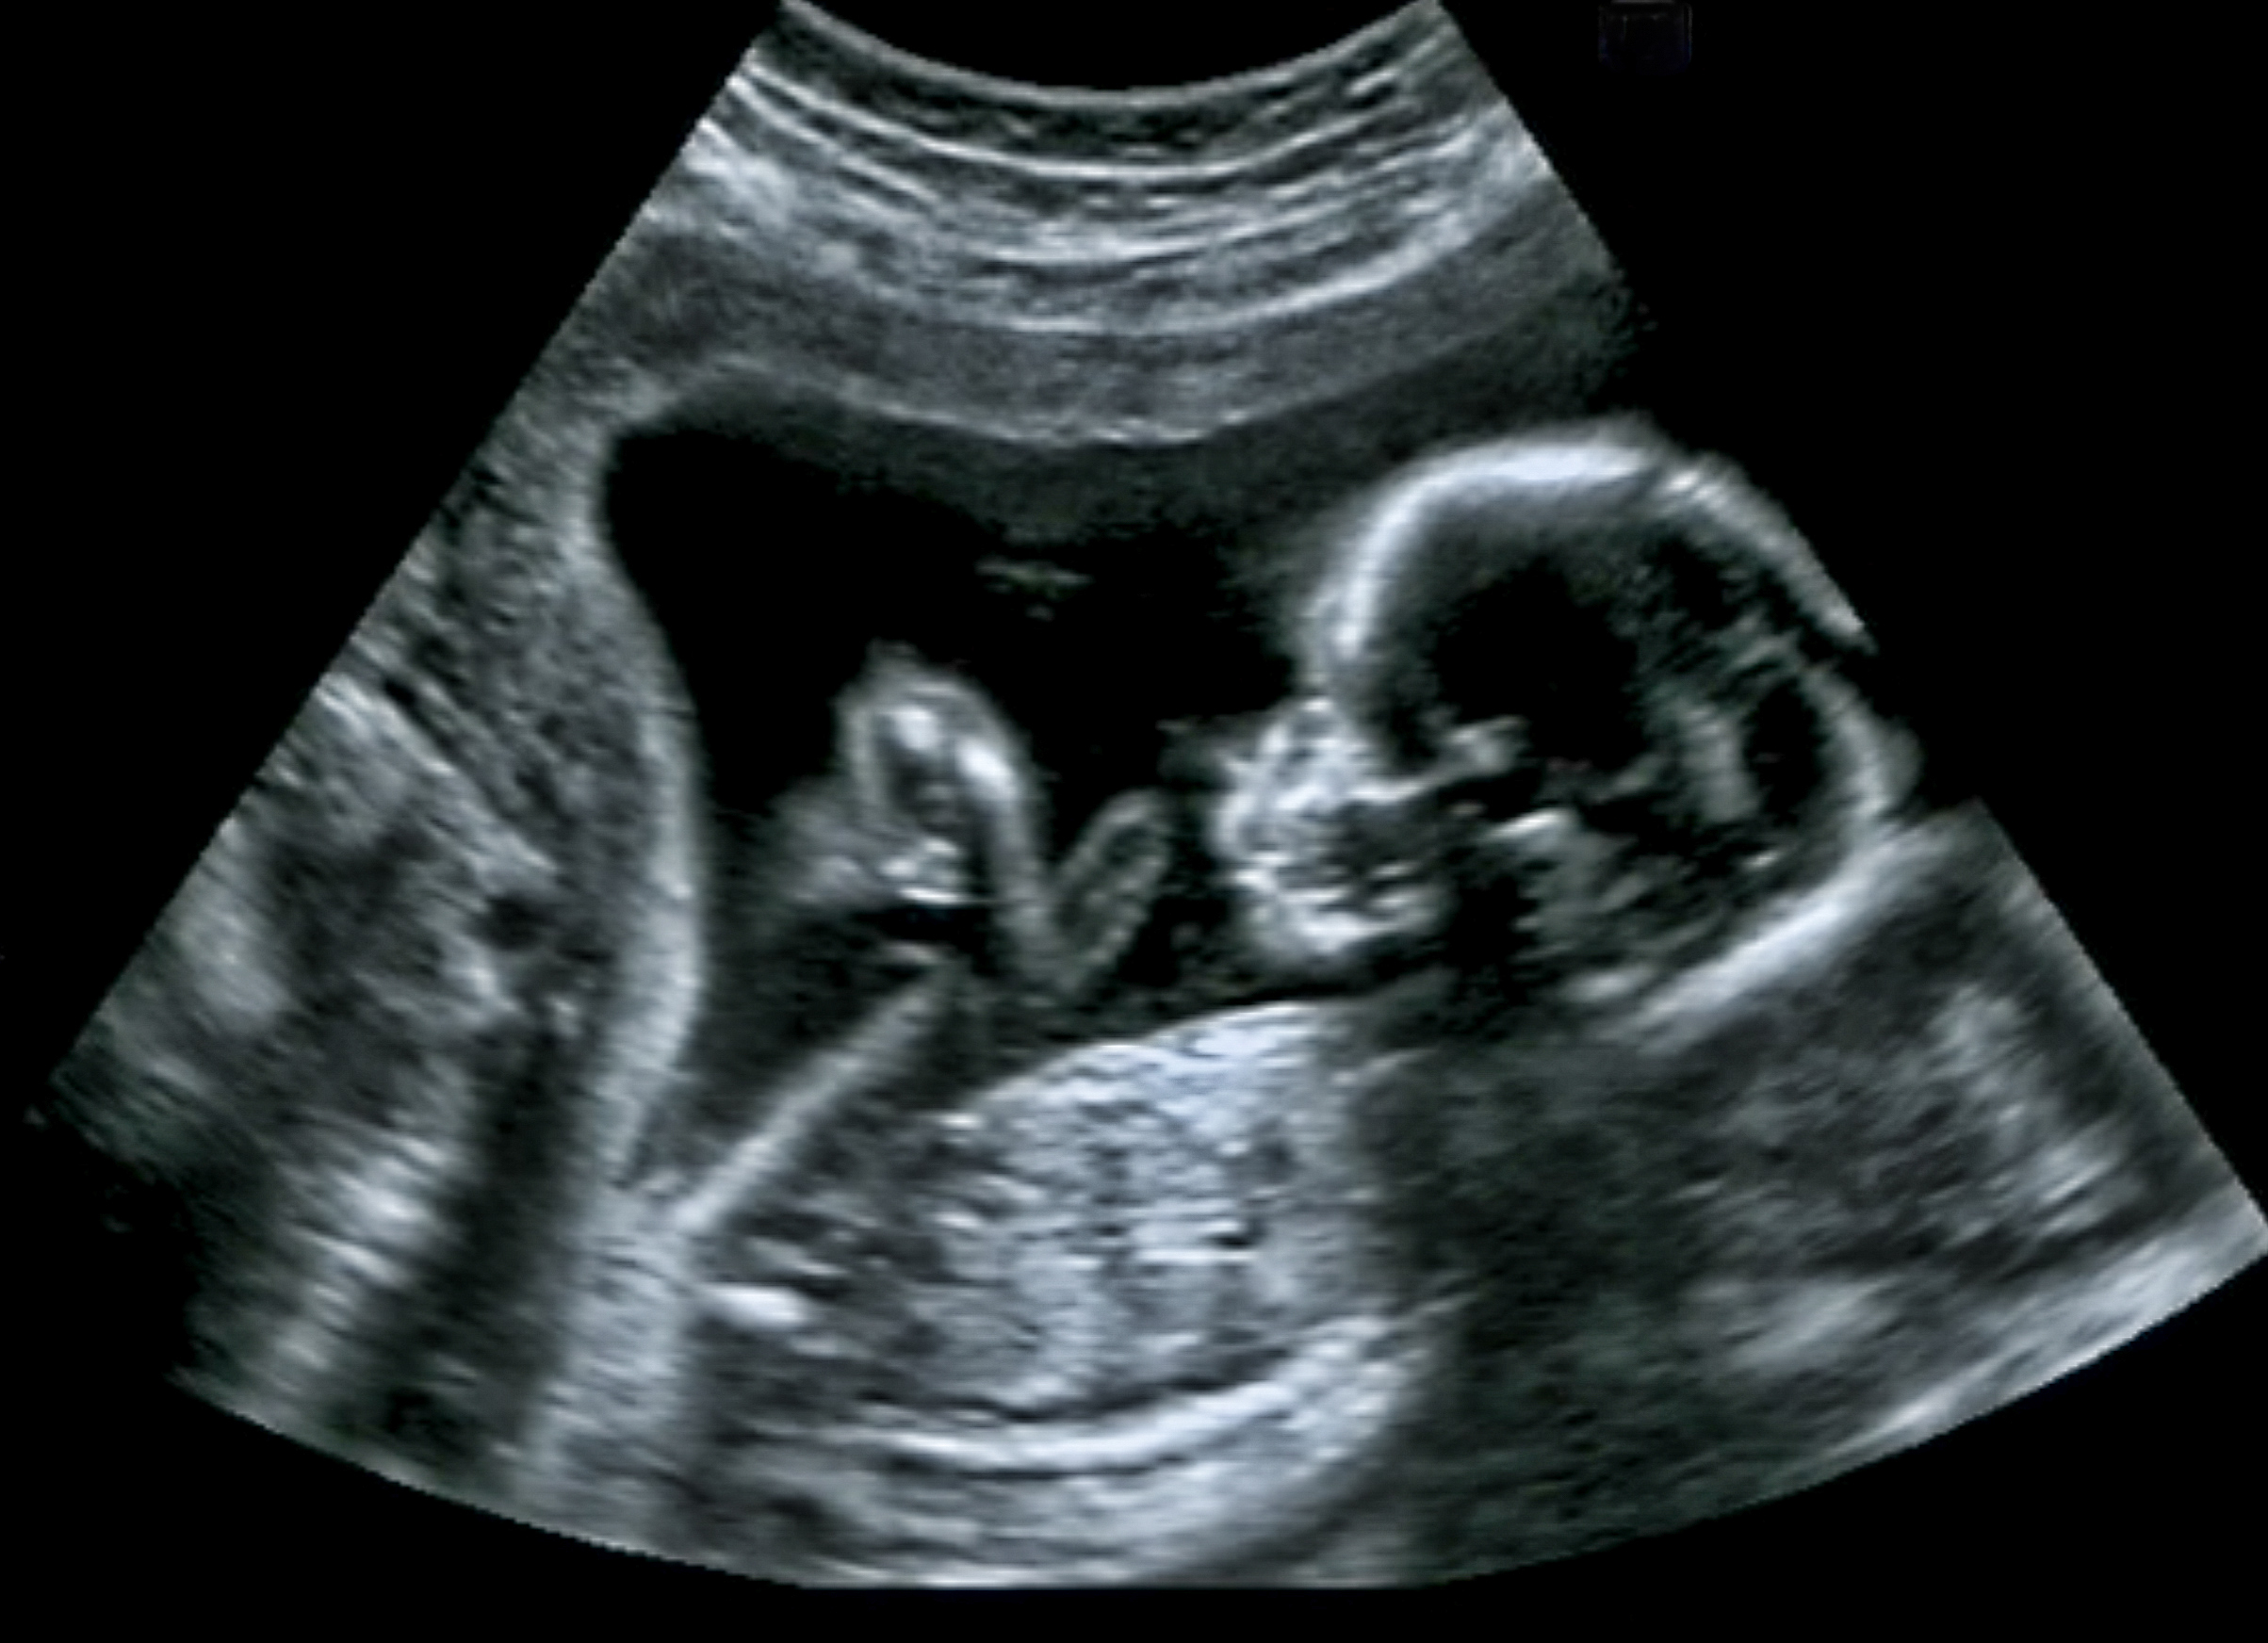

- Images of the body structures (including organs, ligaments, tendons, muscles, and blood vessels) are obtained through specialised equipment using high frequency sound waves.

- The examination is done in real-time, making it possible to evaluate movement.

- Ultrasound does not use ionising radiation and is therefore safe to use in pregnancy.